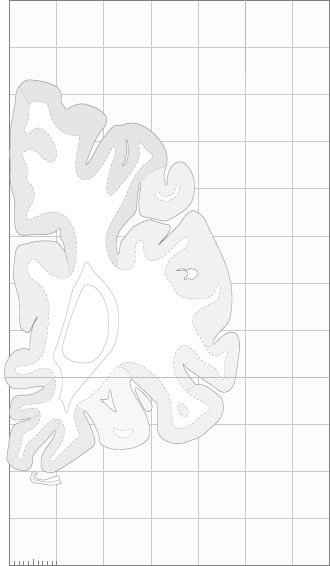

Hi-Resolution Sections · Cells (Nissl Staining) · Virtual Microscopy

Frontal sections (Nissl) from the Atlas Brain:

Schematic

Slice ID:

r1-0149

Plate NR:

05

Position:

-37,4 mm